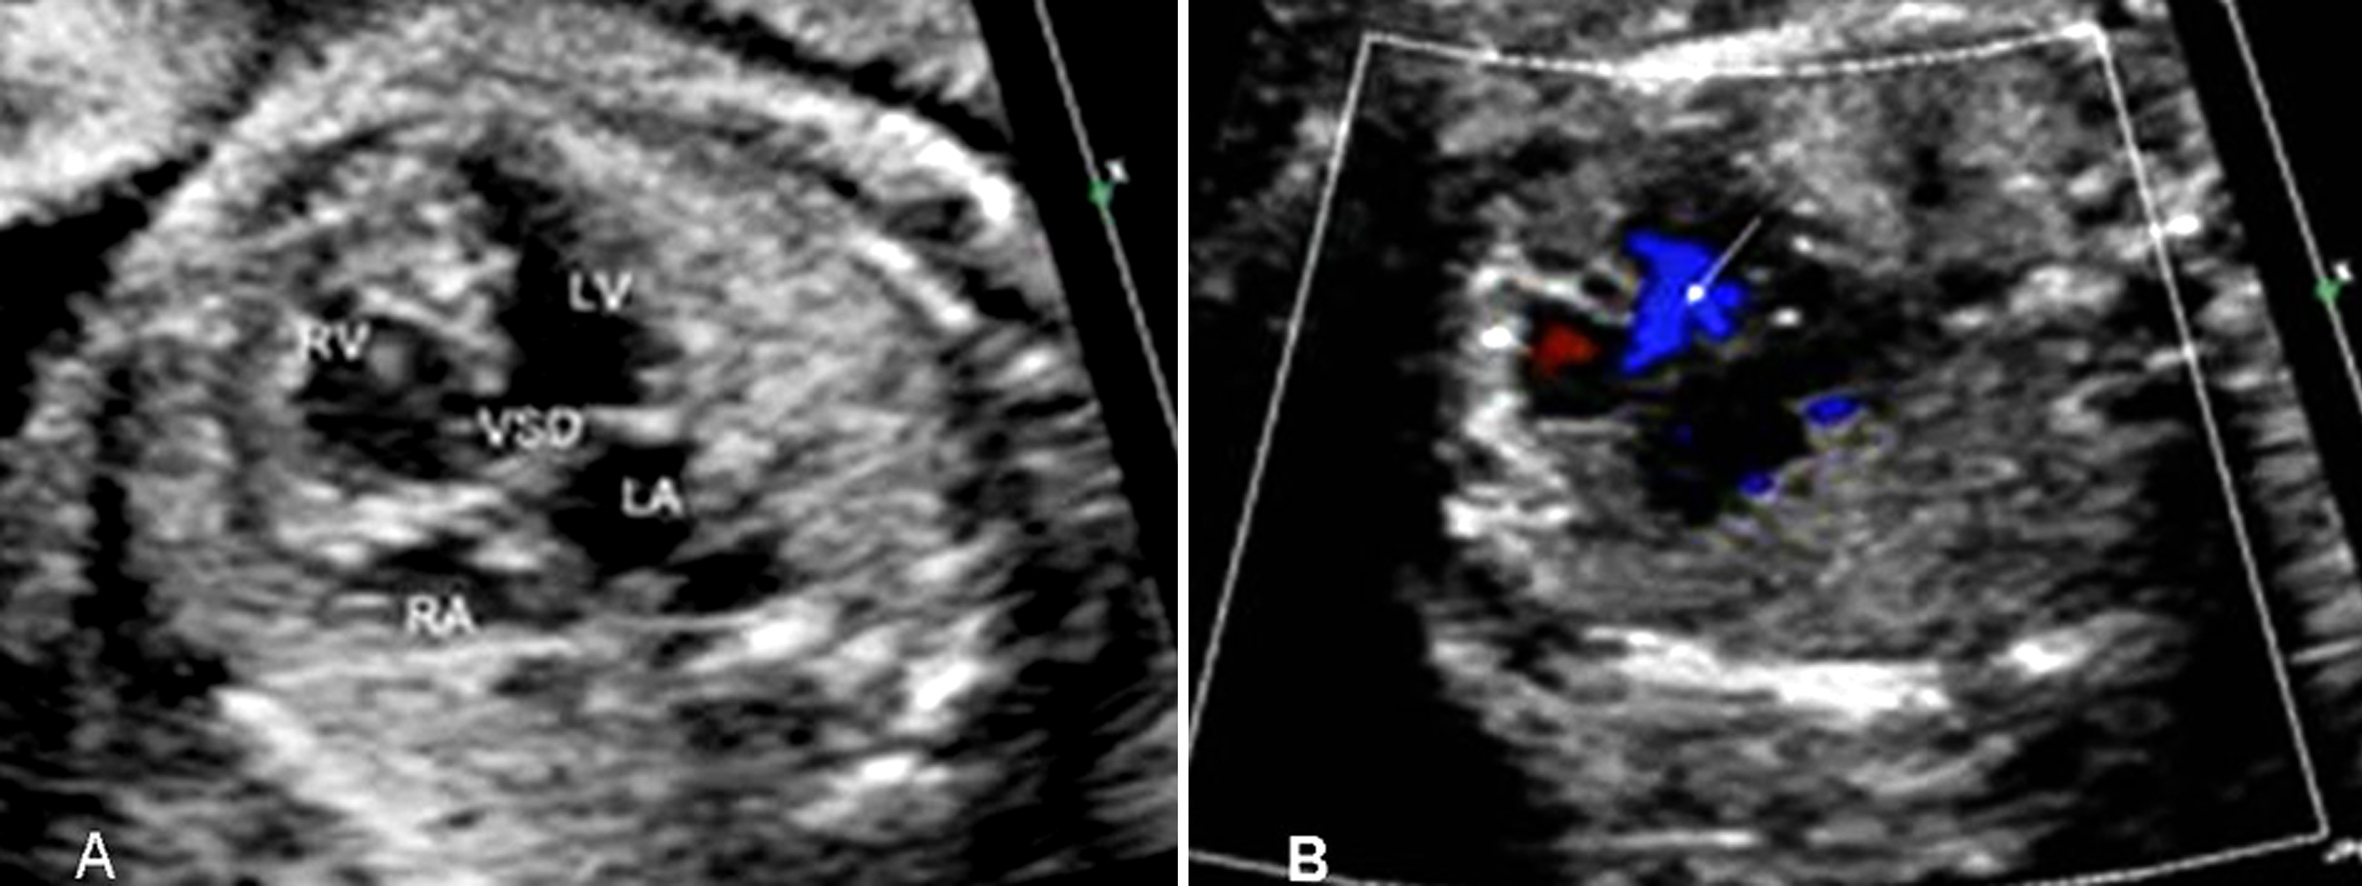

一般5mm以内的VSD在胎儿期容易被漏诊。漏诊原因不仅是由于缺损太小,而且还与是否有室间隔穿隔血流的存在有关。在心尖四腔心切面观,室间隔回声与声束平行,由于超声的侧壁失落效应易使膜部室间隔发生回声失落,出现缺损的假象,此时需改变探头角度以获得胸骨旁四腔心切面观,使得室间隔与声束垂直以观察室间隔的连续性,同时应用彩色多普勒观察是否有穿隔血流,还可应用多普勒时间流速曲线测量穿隔血流以进一步证实。因此有穿隔血流存在是胎内诊断VSD的可靠指标(图1、图2)。

图1 胎儿膜周部室间隔缺损:A:二维超声显示胎儿膜周室间隔缺损;B:为同一剖视面观彩色多普勒血流图